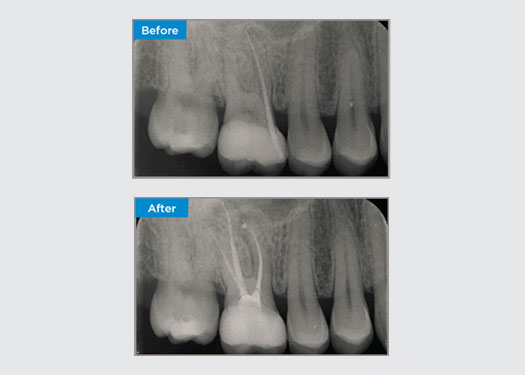

El paciente presentó periodontitis apical asintomática en la pieza dental 34. A partir de la radiografía preoperatoria, se observó que la pieza dental 34 tenía dos raíces visibles. Sin embargo, un escaneo CBCT confirmó un premolar de tres raíces y los canales se dividieron en tres en la raíz media. Una cuidadosa selección de limas es fundamental para este diente delicado.

Dr. Jack Lin, endodoncista, Sídney, NSW Australia

En esta situación, la preservación de la estructura del diente/raíz es esencial para reducir el riesgo de reborde, transporte, cierre, perforación y fractura de la raíz. La selección de casos, el diagnóstico y la planificación previa al tratamiento son importantes. La selección de limas de endodoncia con flexibilidad, eficiencia y respeto por la anatomía de la raíz natural es fundamental.